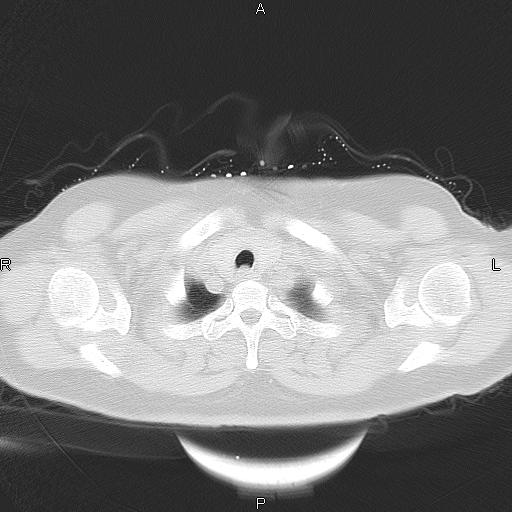

胸腺瘤

女、63Y 双眼睑下垂,早轻晚重。 胸腺瘤???

结果胸腺瘤